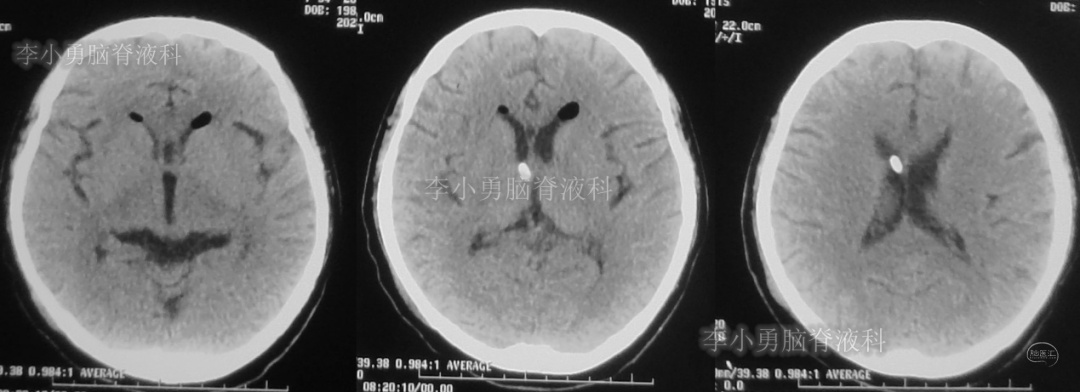

患者于2018年1月29日,突发头痛、头晕、恶心、呕吐,并高热40度。在当地医院门诊输入4天抗生素后发热缓解,但出现了双眼不能上视(眼球不能向上看)。5天后即2018年2月3日,在当地的第1家医院:浙江省海宁市某医院行头颅CT(图-1)发现脑室扩张,当地医院诊断为“梗阻性脑积水”。

图-1:2018年2月3日头颅CT